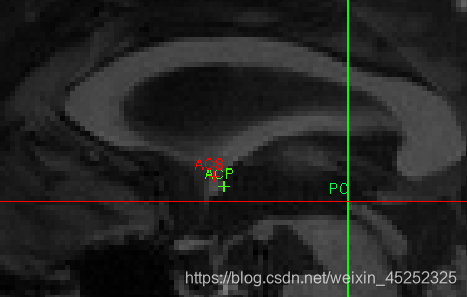

对于这5个点的介绍(图中显示的是矢状面):

一般的nii图中各组织并不是这么明显

AC:

•矢状位:在穹窿下方胼胝体底部寻找AC

•冠状:寻找“胡须”

•轴向:寻找半球间的连接

① 使AC在十字准线的焦点处居中(轴向和冠状)

② 向上移动,直到AC在轴向视图中消失,然后向下移动1像素

③ 设置AC上边缘(superior edge)

④ 将焦点移回AC中间

⑤ 向后移动直到AC在冠状面上消失;然后往前1像素

⑥ 设置AC后缘(posterior margin)

尽量把图放大来选点

找到AC superior edge,点击set

找到AC posterior edge,点击set

(4)第二个目标是标记PC inferior edge

•这更难,因为PC在1毫米分辨率下显示不好

•幸运的是,PC始终位于脑导水管的顶部,这确实显示得很好(至少,如果脑脊液被MRI脉冲序列适当抑制的话)

因此,如果你看不到PC,就在脑导水管顶部找到中矢状位,标记为PC下缘(inferior edge)